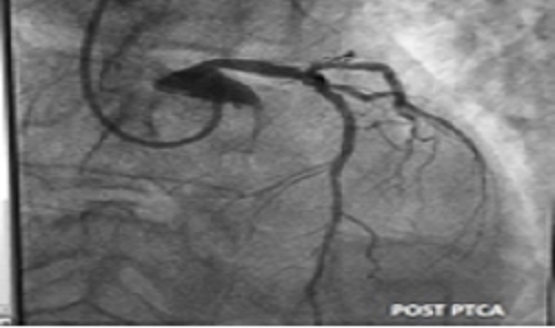

A 52 year old male Mr. Shantilal Shah had anterior wall MI thrombolysed with STK. Coronary angiography showed critical tripple vessel disease.

Cardiac surgeon refused CABG surgery at higher cardiac center in view of severe kyphoscoliosis. Cardiac anesthetic refused case due to restrictive lung disease and inability to give general anesthesia.

This challenging case came to Dr. Vivek Gaikwad & Team at platinum hospital vasai for revasculation. Hence we planned to do angioplasty. Left Radial access was obtained in view of tortuous aorta & inability to do angioplasty through femoral artery. PTCA TO LAD & LCX DONE propped up 30- degree position with two stents with good results.